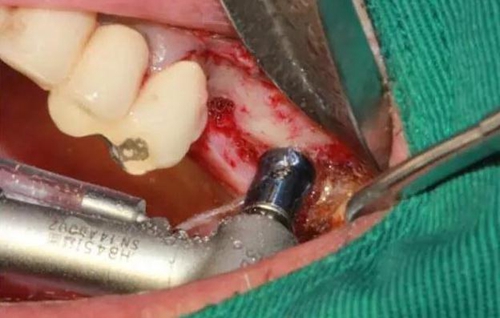

剝離右上6,7頰側(cè)

MASAL工具內(nèi)提升永磁鉆--這就是本病例改良開窗的關(guān)鍵

安全地在上頜竇外壁鉆一個(gè)洞

分離洞邊緣膜